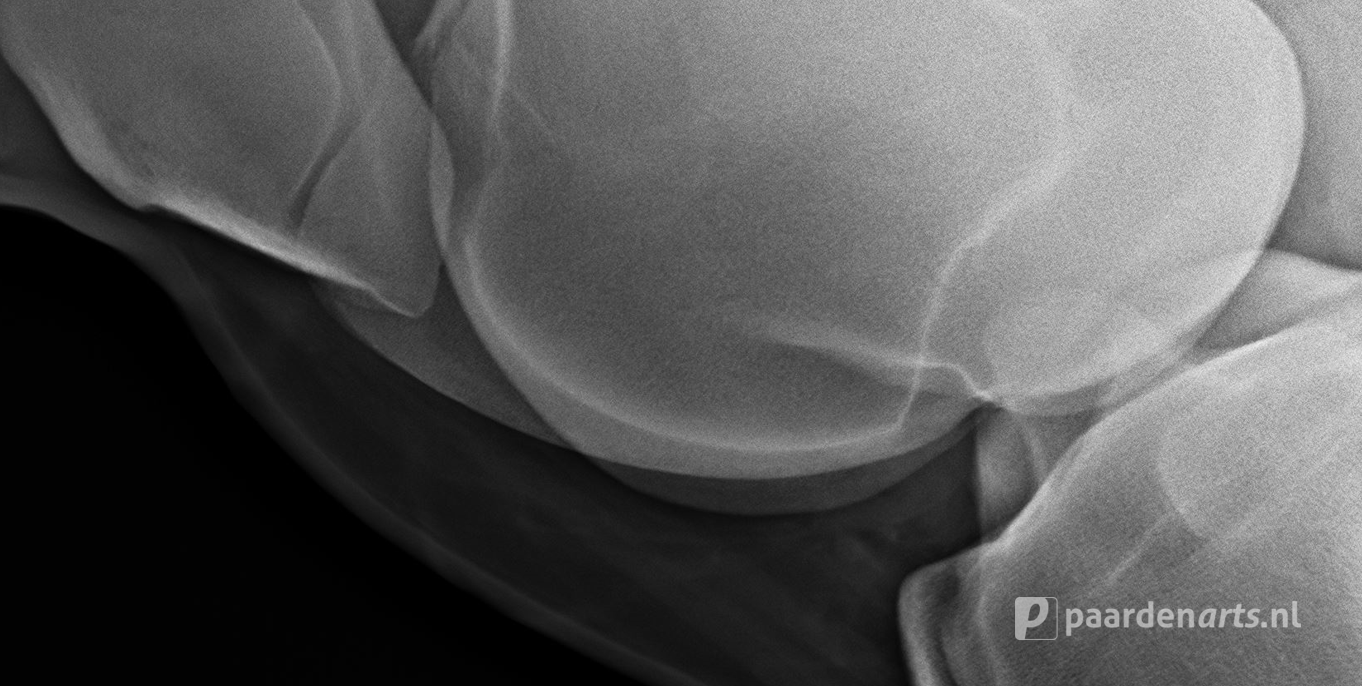

Bij een paard dat hoefbevangen is, zal er een röntgenfoto gemaakt moeten worden om vast te kunnen stellen in welke fase de hoefbevangenheid is. Op de beelden is dan precies te zien welke vorm van hoefbevangenheid het paard heeft, hoe ernstig de situatie is en of er sprake is van bijvoorbeeld kanteling of verzakking van het hoefbeen.